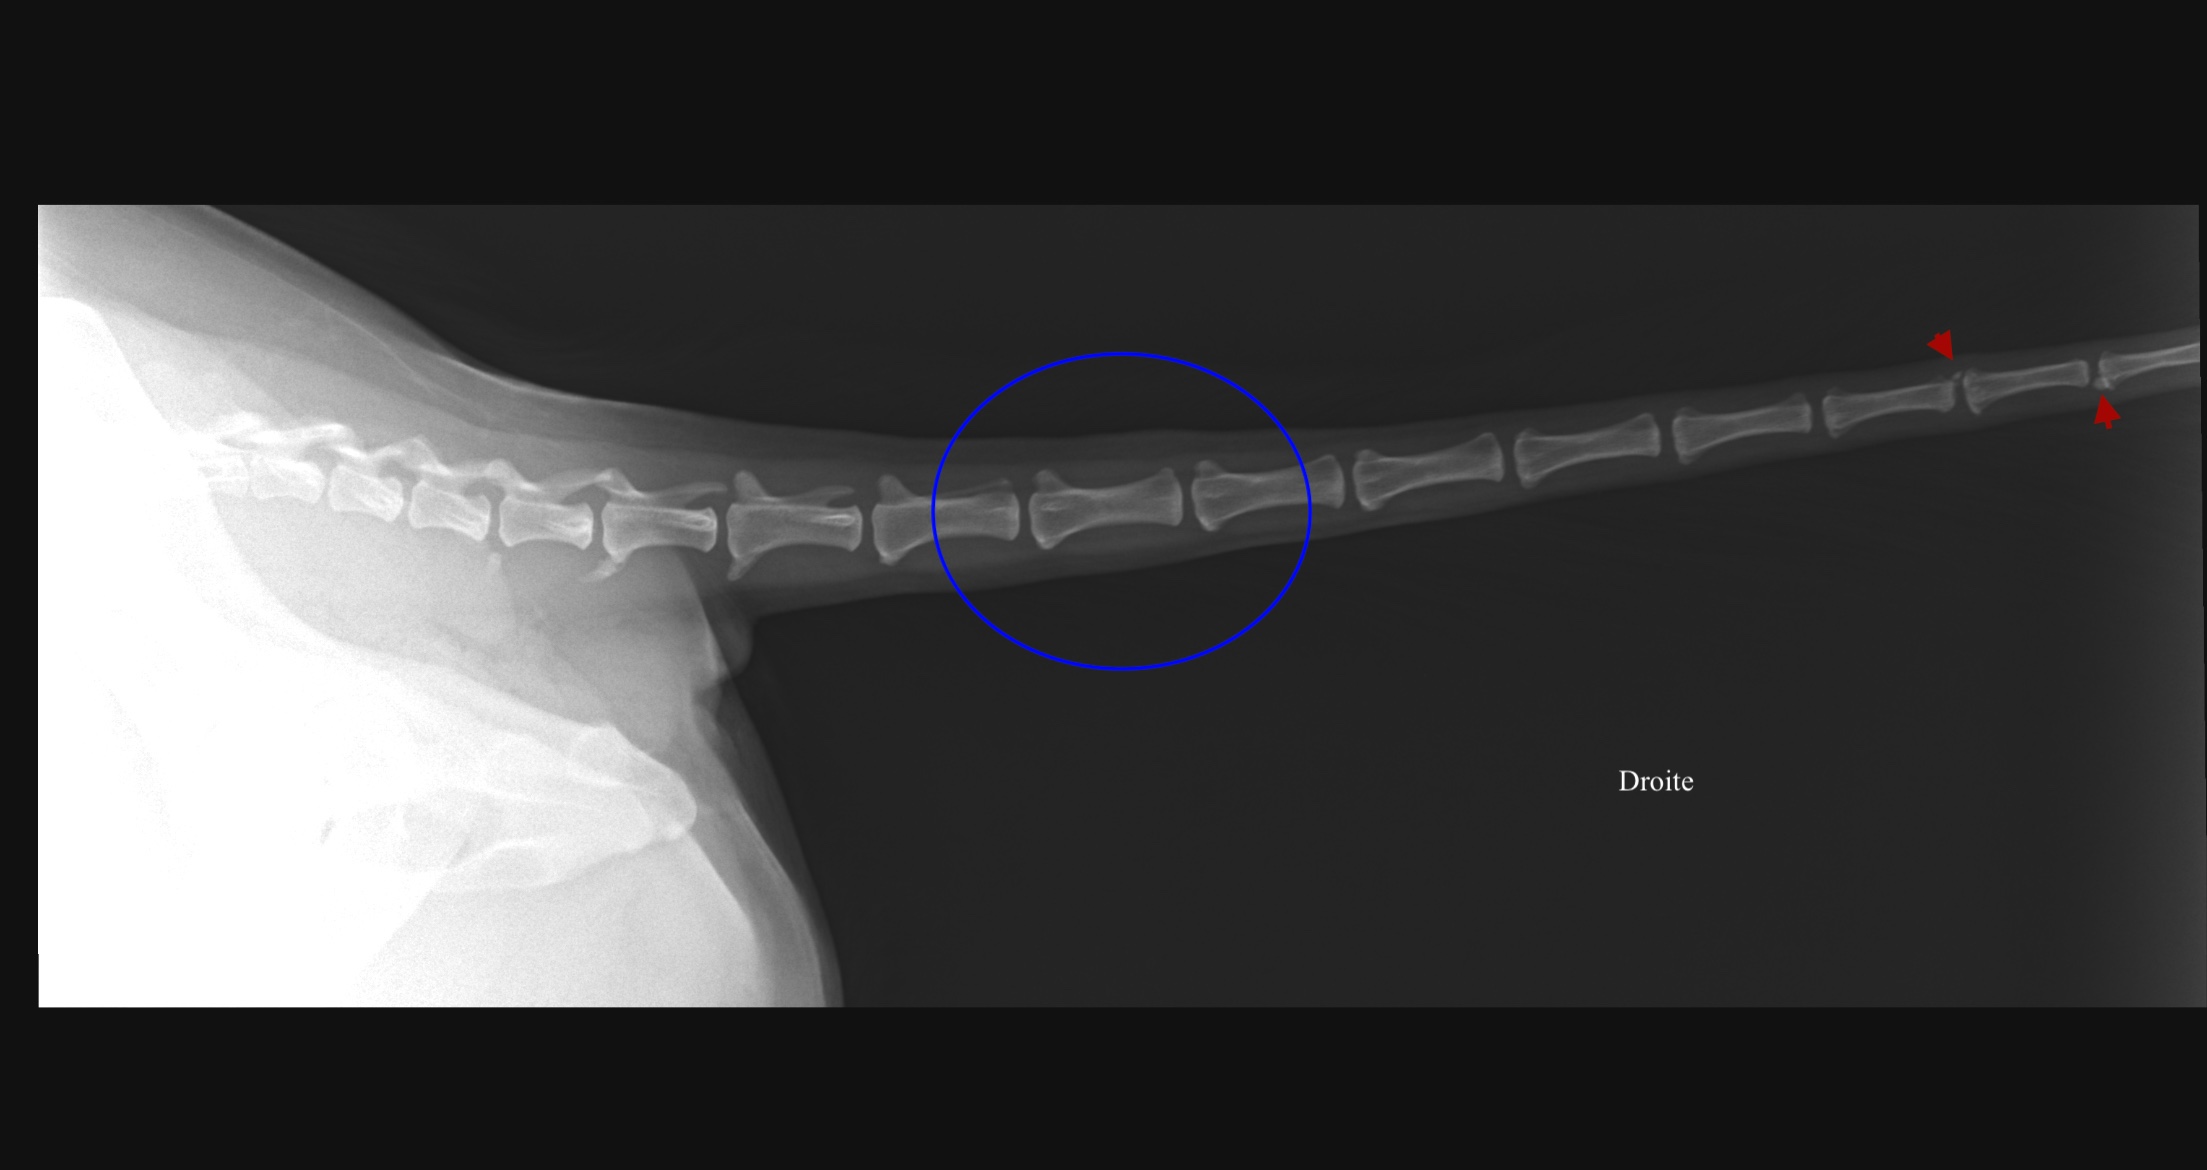

Des radiographies en vue dorso-ventrale et de profil droit de la queue sont réalisées Elles montrent l’intégrité de tous les espaces intervertébraux avec un alignement correct de la queue. Une discrète prolifération osseuse entre les vertèbres caudales Cd14-15, Cd15-16 et Cd16-17 est visualisée, pouvant être compatible avec des changements dégénératifs (ostéophytes). Aucune anomalie des structures extra- osseuses n’est visible sur ces clichés radiographiques. La jonction lombosacrée ne présente pas d’anomalie radiographique. Ces images radiographiques ne sont pas en mesure d’expliquer les symptômes.